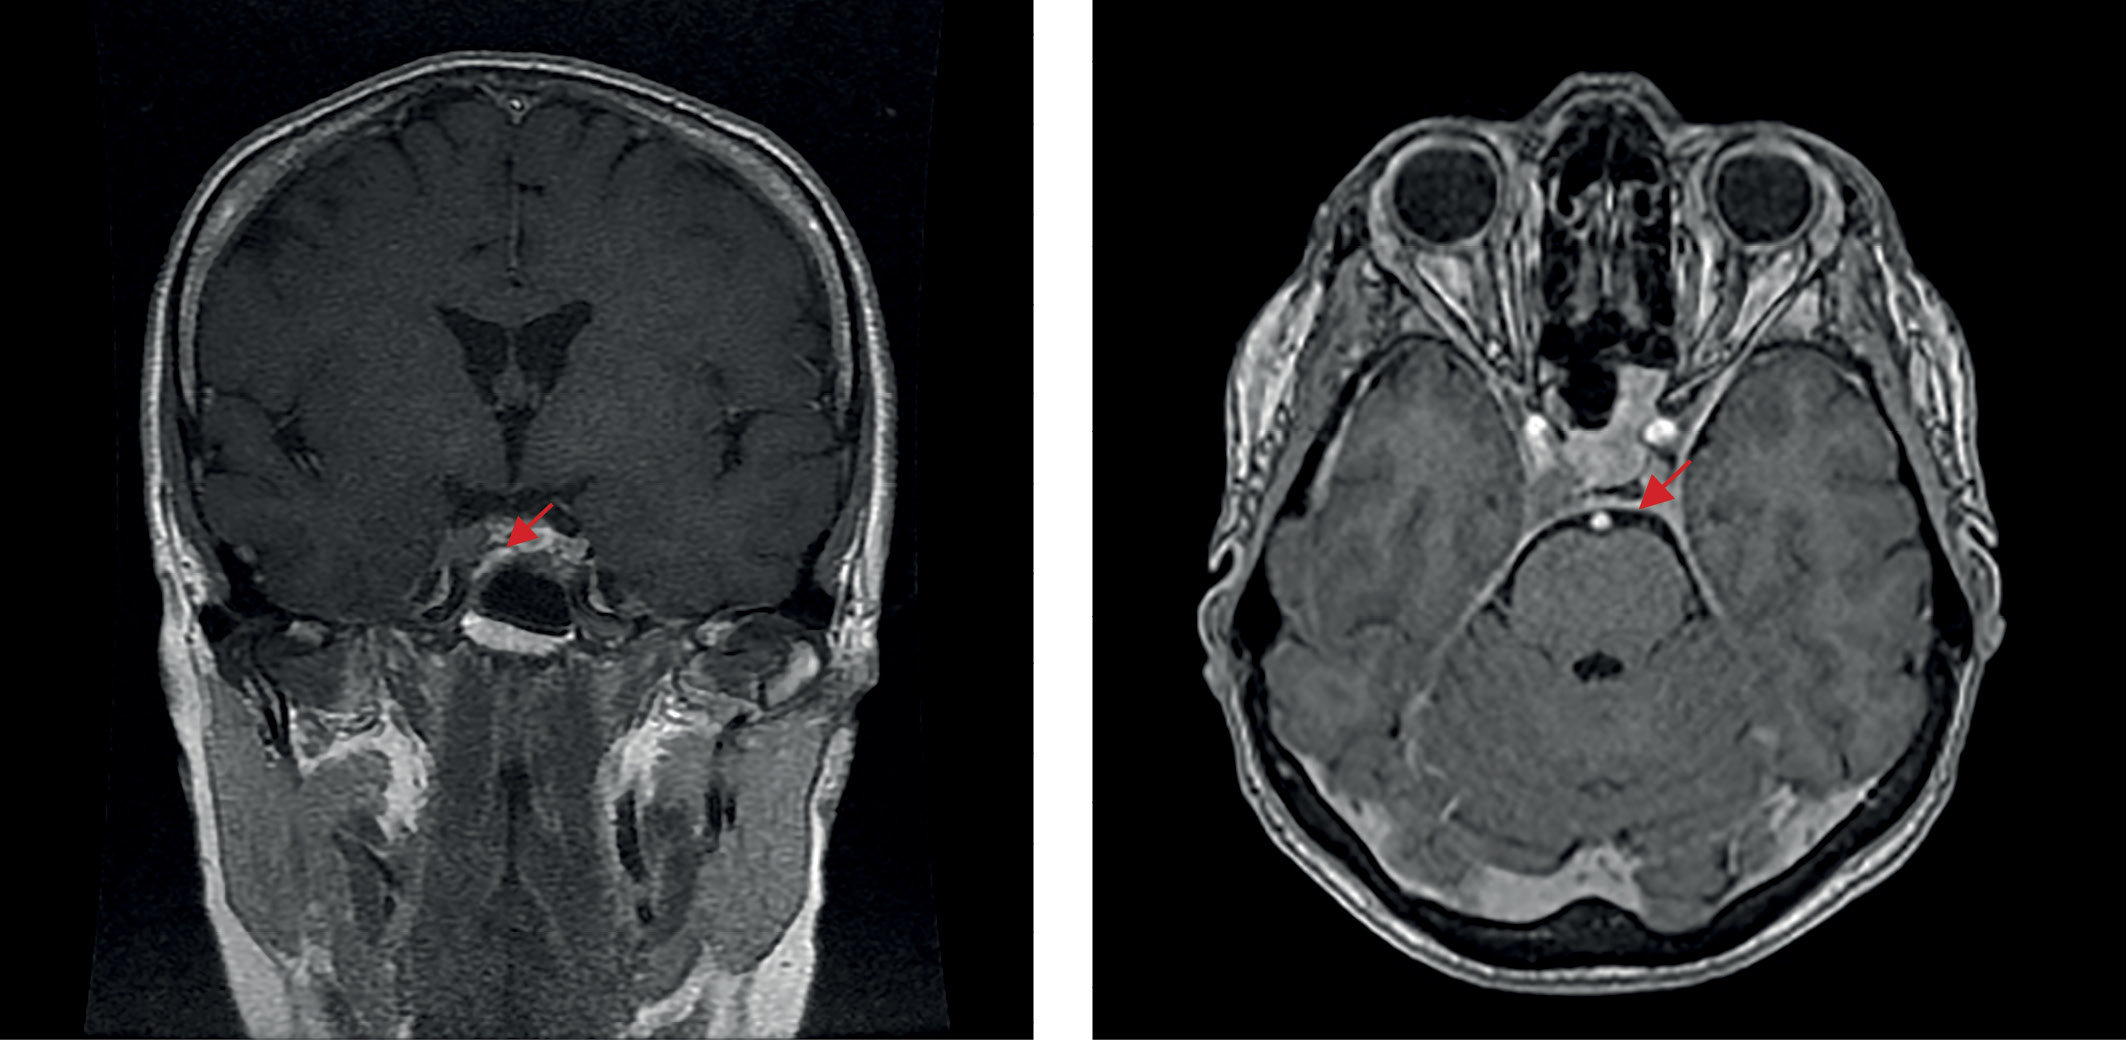

С ноября 2017 г. стала отмечать изменения внешности в виде отечности лица и прибавки массы тела без изменения привычной диеты. Исходно и на фоне прибавки массы тела индекс массы тела (ИМТ) — норма, нарушений углеводного обмена и артериальной гипертензии (АГ) в анамнезе не было. Обращало внимание распределение жировых отложений преимущественно в области лица и живота. Кроме того, пациентку беспокоили жалобы неврологического характера (онемение конечностей, нарушения координации движений), с которыми обратилась к неврологу. По результатам проведенной МРТ головного мозга в 2018 г. выявлена микроаденома гипофиза размерами 9×6×6 мм (рис. 1). Гормональные исследования на предмет активности новообразования не проводили, специфического лечения назначено не было.

Рисунок 1. МРТ головного мозга до операции (трансназальной аденомэктомии), 2018 г.

1. Рисунок 1. МРТ головного мозга до операции (трансназальной аденомэктомии), 2018 г